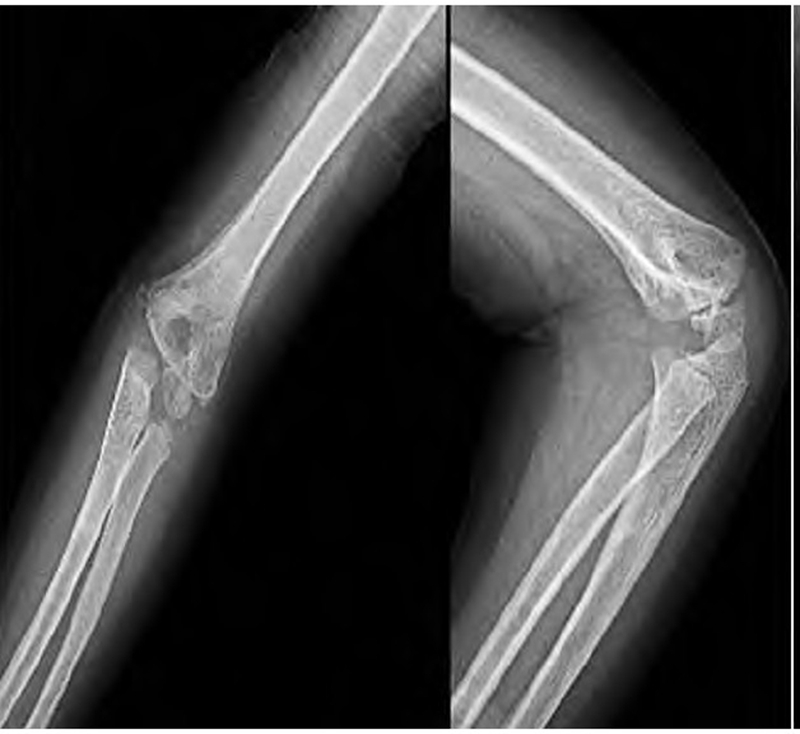

术后予止血、消肿、口服甲钴胺营养神经及抗感染对症治疗,定期创口换药。术后复查DR片提示骨折断端对位对线可,内固定位置良好,桡骨头复位良好,肘关节位置良好(图2)。术后7周拔除克氏针进行功能训练(图3)。术后3个月复查DR片提示骨折断端骨折线已消失,可见较多骨痂影(图4)。随访3年10个月,患儿无肘内、外翻畸形,无肘关节及腕关节活动受限(图5),肘关节 Mackay功能评分为优。

图2 术后 DR片示骨折断端对位对线可,内固定位置良好,异物完整取出

图3 术后7周 DR片示内固定已完整取出,肘关节位置良好